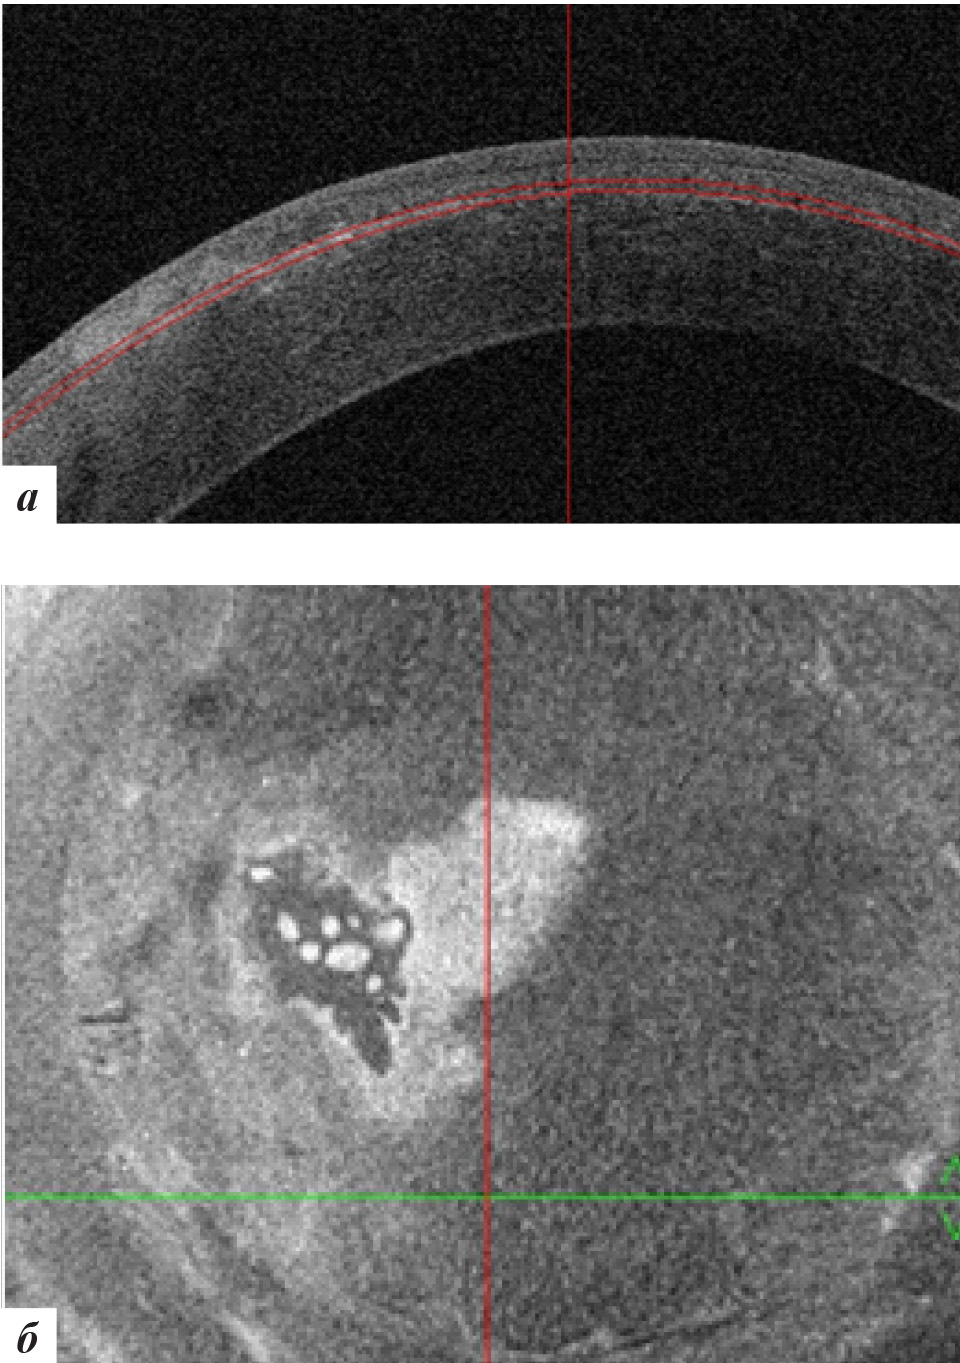

Рис. 9. Данные ОКТ роговицы левого глаза через 9 месяцев после лечения: а – горизонтальная проекция, б – фронтальная проекция

При офтальмобиомикроскопии глаз спокоен, в роговичном интерфейсе в ЦОЗ и параоптической зоне отмечена элиминация эпителиальных клеток с формированием стойких облаковидных помутнений (рис. 8) с отсутствием перифокального отека. ОКТ-сканирование передней поверхности роговицы также подтвердило отсутствие признаков рецидива врастания (рис. 9). С рекомендациями использования слезозаменителей пациентка выписана по месту жительства.

При офтальмобиомикроскопии OS в роговичном интерфейсе в центральной оптической и параоптической зонах отмечалось стойкое облаковидное помутнение при отсутствии рецидива роста эпителиальных клеток (рис. 10), подтвержденное данными ОКТ роговицы (рис. 11).

Рис. 11. Данные ОКТ роговицы левого глаза через 18 месяцев после лечения: а – горизонтальная проекция, б – фронтальная проекция